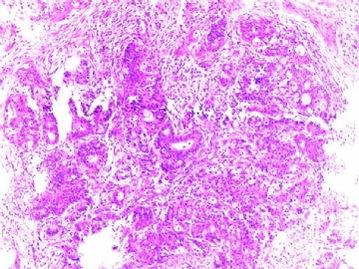

首先,得先了解一下什么是子宫腺肌症。简单来说,它就是子宫壁上的腺体长错了地方,跑到肌层里去了。这听起来可能有点难以理解,但别急,我来给你举个例子。想象子宫就像一个房子,腺体就像是房子的装饰品,本来应该贴在墙上的,结果却跑到地板上了。这样一来,房子(子宫)就会变得不舒服,甚至可能会漏水(月经异常)。